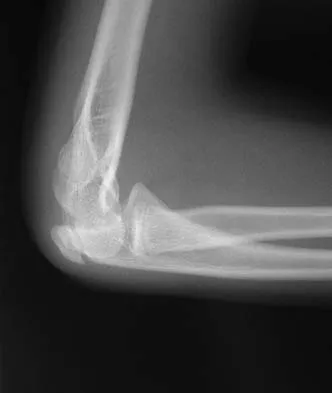

Figure 38 shows the radiograph of a 16-year-old wrestler who injured his elbow when he was thrown to the mat by his opponent. To minimize additional trauma to the medial soft tissues, the elbow should be reduced in